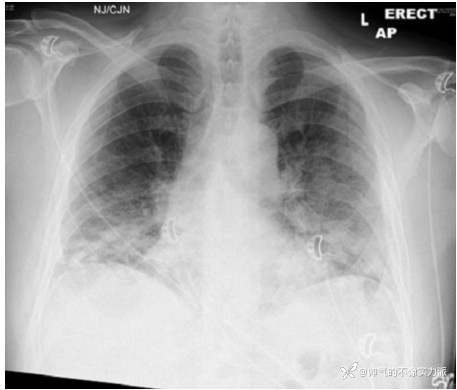

病例1:60岁男性,不吸烟,无其他疾病病史。感染新冠病毒后胸闷憋喘,遂至医院急诊就诊,测指氧饱和度为88%,动脉血气分析(FiO2 35%):pH 7.50,PaO2 51 mmHg,PaCO2 31.5 mmHg,HCO3- 26.6 mmol/L,BE 2.5 mmol/L,Lac 2.2 mmol/L。胸片示双下肺广泛磨玻璃影(图2)。入院1天后,患者氧合下降明显,需氧量增加,完善CT肺动脉造影(CTPA)检查未发现肺栓塞,广泛的磨玻璃改变及小叶间隔增厚(图3)。

图2 患者胸片